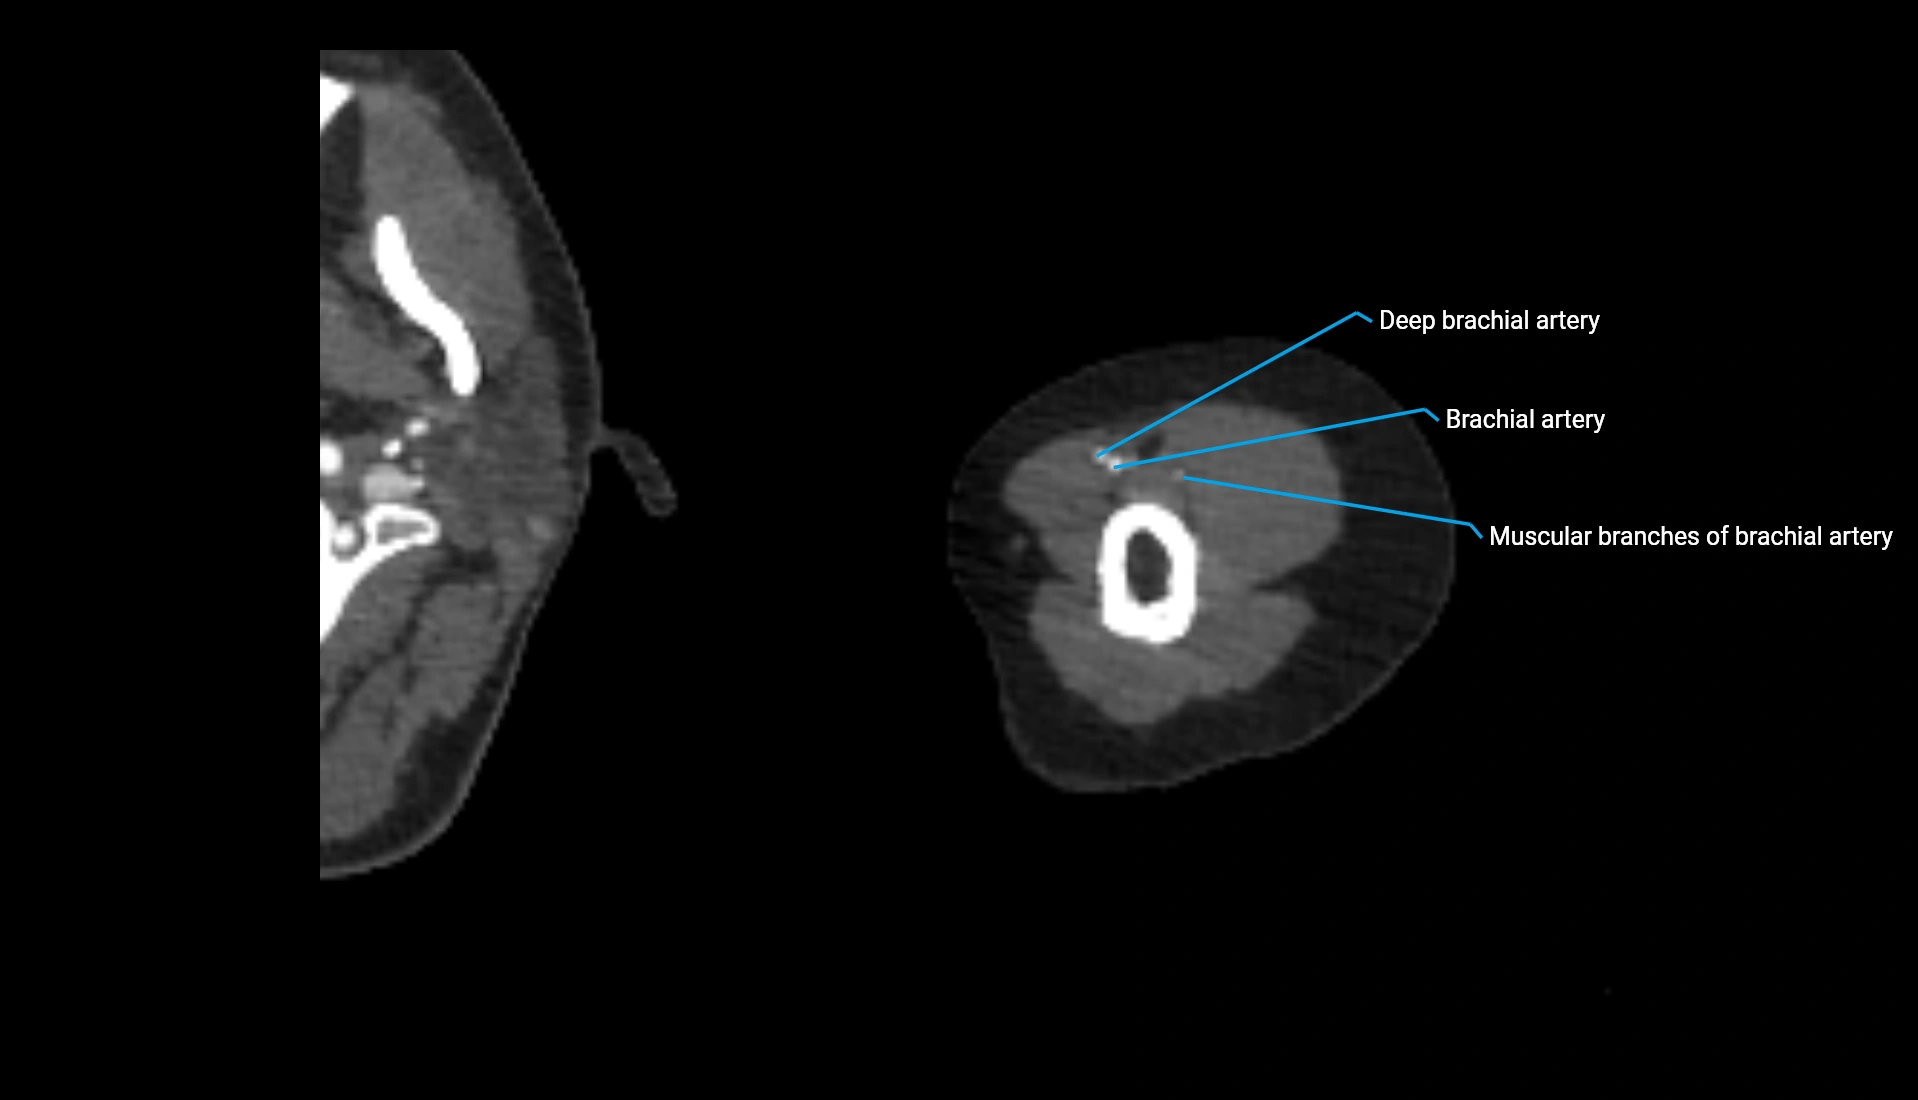

CT Appearance

Non-Contrast CT:

• Cortex: High-density, sharply defined

• Subchondral bone: Dense cancellous matrix

• Articular surface: Smooth concave contour articulating with the capitellum

• Excellent for evaluating bone integrity, alignment, and subtle fractures